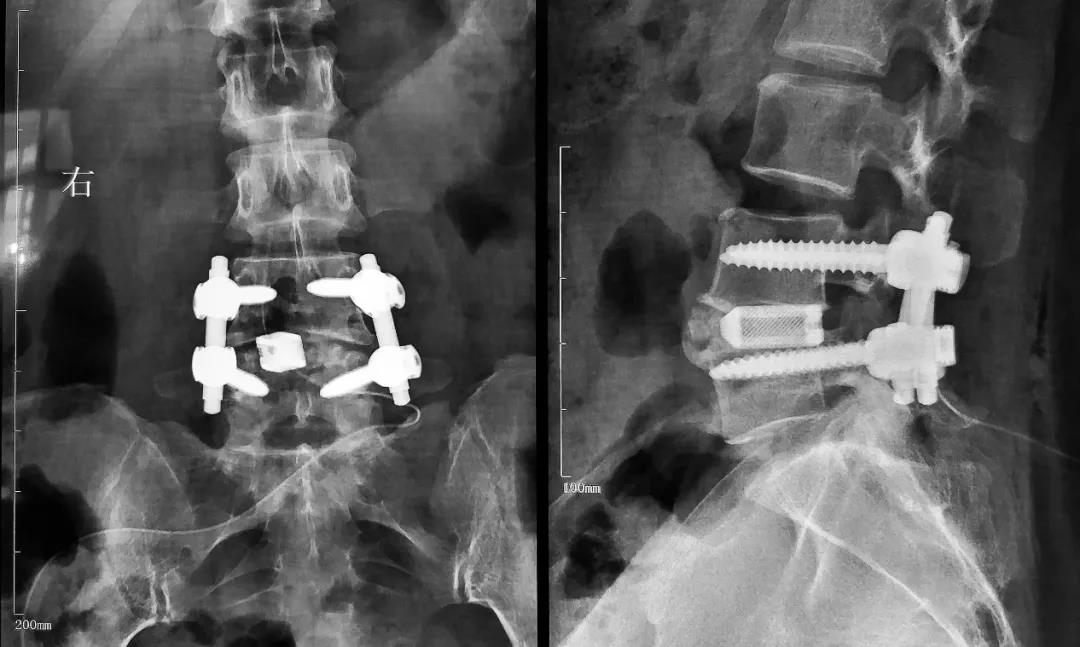

南极熊获悉,2021年9月,中诺恒康3D打印“椎间融合器”顺利获得国家食品药品监督管理局批准上市。该证的获批标志着国内首家通过增材制造工艺生产的无植骨窗“椎间融合器”开始走向临床,同时中诺恒康成为国内第二家获得同类产品注册证的企业,具有里程碑式的意义。

据南极熊了解,中诺恒康研发生产的这款椎间融合器,是使用EBM电子束金属3D打印钛合金材料而成,特点包括:

孔径300-800μm,孔隙率70-80%;

是国内首款无植骨窗使用增材制造工艺生产的融合器产品;

具备良好的生物相容性;

类松质骨的弹性模量;

表面微孔结构提供良好的初始稳定性;

同时具备多型号、多规格能满足多种手术需求。